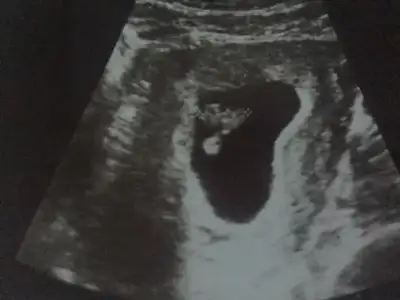

merhabalar bende tahmin alabilir miyim?

ilk olan 6 yada 7 haftalıktı son lan 12 haftalık